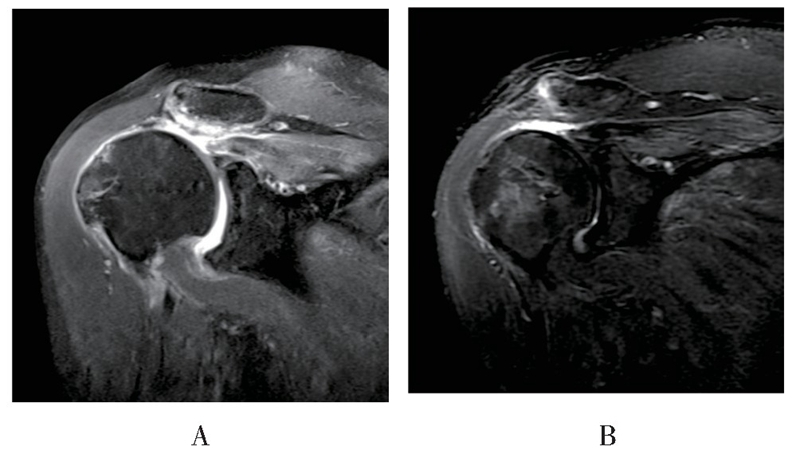

MRI随访见18例患者重建组织结构完整,愈合率达85.7%(18/21),3例出现明显结构失败,但失败患者功能恢复良好,未诉明显不适,因此未行翻修手术(见图5、图6)。

图5 患者女,67岁,末次随访时斜冠状位MRI显示右肩术后重建结构连续性完整A:术前磁共振影像,B:术后磁共振影像

图6 患者男,56岁,术后6个月随访时斜冠状位MRI显示右肩术后重建结构失败A:术前磁共振影像,B:术后磁共振影像